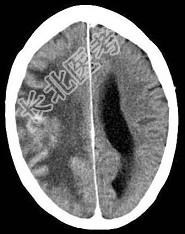

- 单项选择题有关脑转移瘤(如图所示),瘤周围水肿属于 ( )

D、血管源性水肿